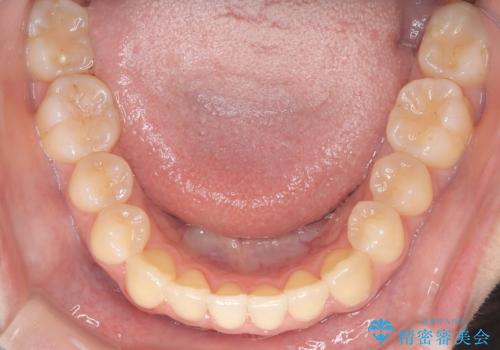

- 患者様は左上の八重歯を気にされて来院されました。八重歯による歯列の乱れだけでなく、翼状捻転(歯がねじれるように生えている状態)も見られました。目立たない矯正を希望されていたため、**インビザライン(マウスピース矯正)**を選択し、左上の小臼歯を抜歯してスペースを作りながら歯を並べる治療計画を立てました。しかし、治療の途中で翼状捻転の改善が十分に進まなかったため、患者様の希望も踏まえ、上顎のみワイヤー矯正に変更することとなりました。

治療開始時はインビザラインを使用し、全体の歯並びを整えながら抜歯スペースを活用して歯を後方へ移動させました。しかし、左上の八重歯のねじれが強く、マウスピースのみでは十分にコントロールできないことが判明。そこで、より細かく歯を動かすために上顎のみワイヤー矯正へ切り替えました。ワイヤー矯正によって翼状捻転も改善し、最終的にバランスの取れた歯並びと噛み合わせを実現。患者様からは「長い治療だったけれど、しっかり整って満足」と嬉しいお言葉をいただきました。